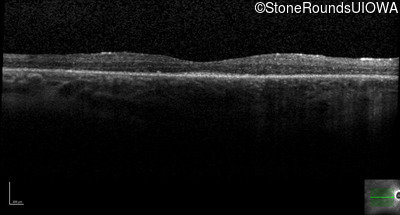

Optical Coherence Tomography - Right - 20/50

Exemplar / OCT Stack

OCT Stack